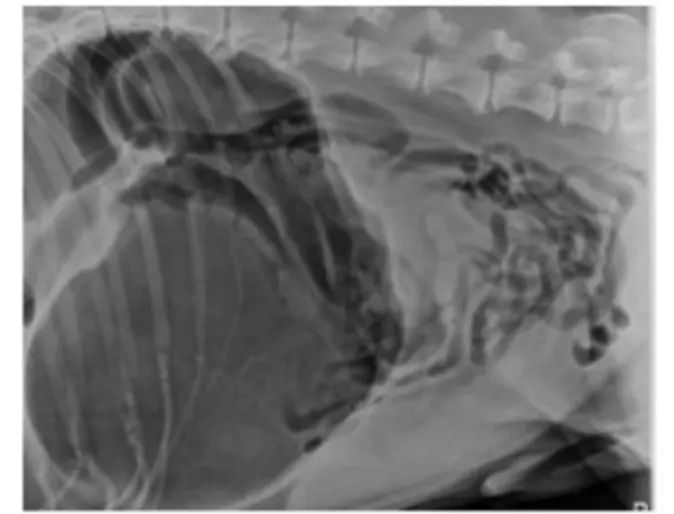

The diagnosis of GDV relies on the combination of a veterinarian’s physical exam and x-rays. On physical exam, a veterinarian may note evidence of dehydration or signs of shock (rapid heart rate, weak pulses, pale gums, and difficulty breathing). An enlarged, gas filled stomach can often be felt on abdominal palpation. Radiographs (x-rays) of a dog’s abdomen will confirm the presence of a dilated and twisted stomach as GDV has a characteristic appearance (“double bubble” or “Popeye’s arm”) on radiographs (compare Figures 1 and 2).

Figure 1. Abdominal radiograph of a dog with a gastric dilatation-volvulus. Note the large dark gas-filled stomach, as compared to Figure 2.